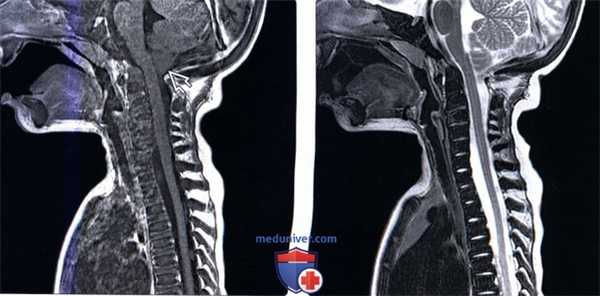

(Слева) Т1-ВИ, сагиттальная проекция (инфантильный остеопетроз): снижение интенсивности сигнала костного мозга всех костей, отражающее сочетание диффузного замещения костного мозга и склероза костей. Миндалины мозжечка эктопированы, что скорее всего является следствием костных изменений задней черепной ямки.

(Справа) Т2-ВИ, сагиттальная проекция (инфантильный остеопетроз): аномальное снижение интенсивности сигнала костного мозга всех костей, включая позвоночник, основание черепа, грудину, что связано с замещением костного мозга и склерозом костей.